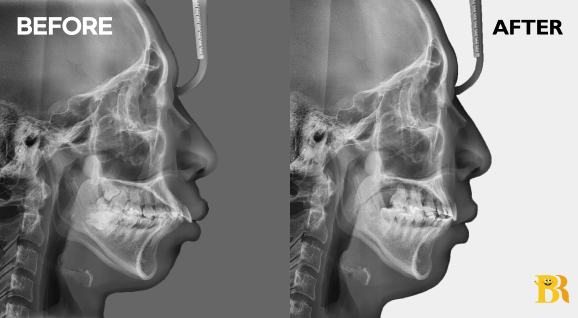

[상악 전치부 매복치를 동반한 케이스] 윗니 2곳에 발치 및 전치부 후방이동으로 돌출입을 해결하고 치열을 고르게 만들었습니다

[상악 전치부가 앞쪽으로 크게 뻗은 케이스] 입술이 도드라져 보여서 발치교정으로 앞니의 각도를 감소시켜 주었습니다